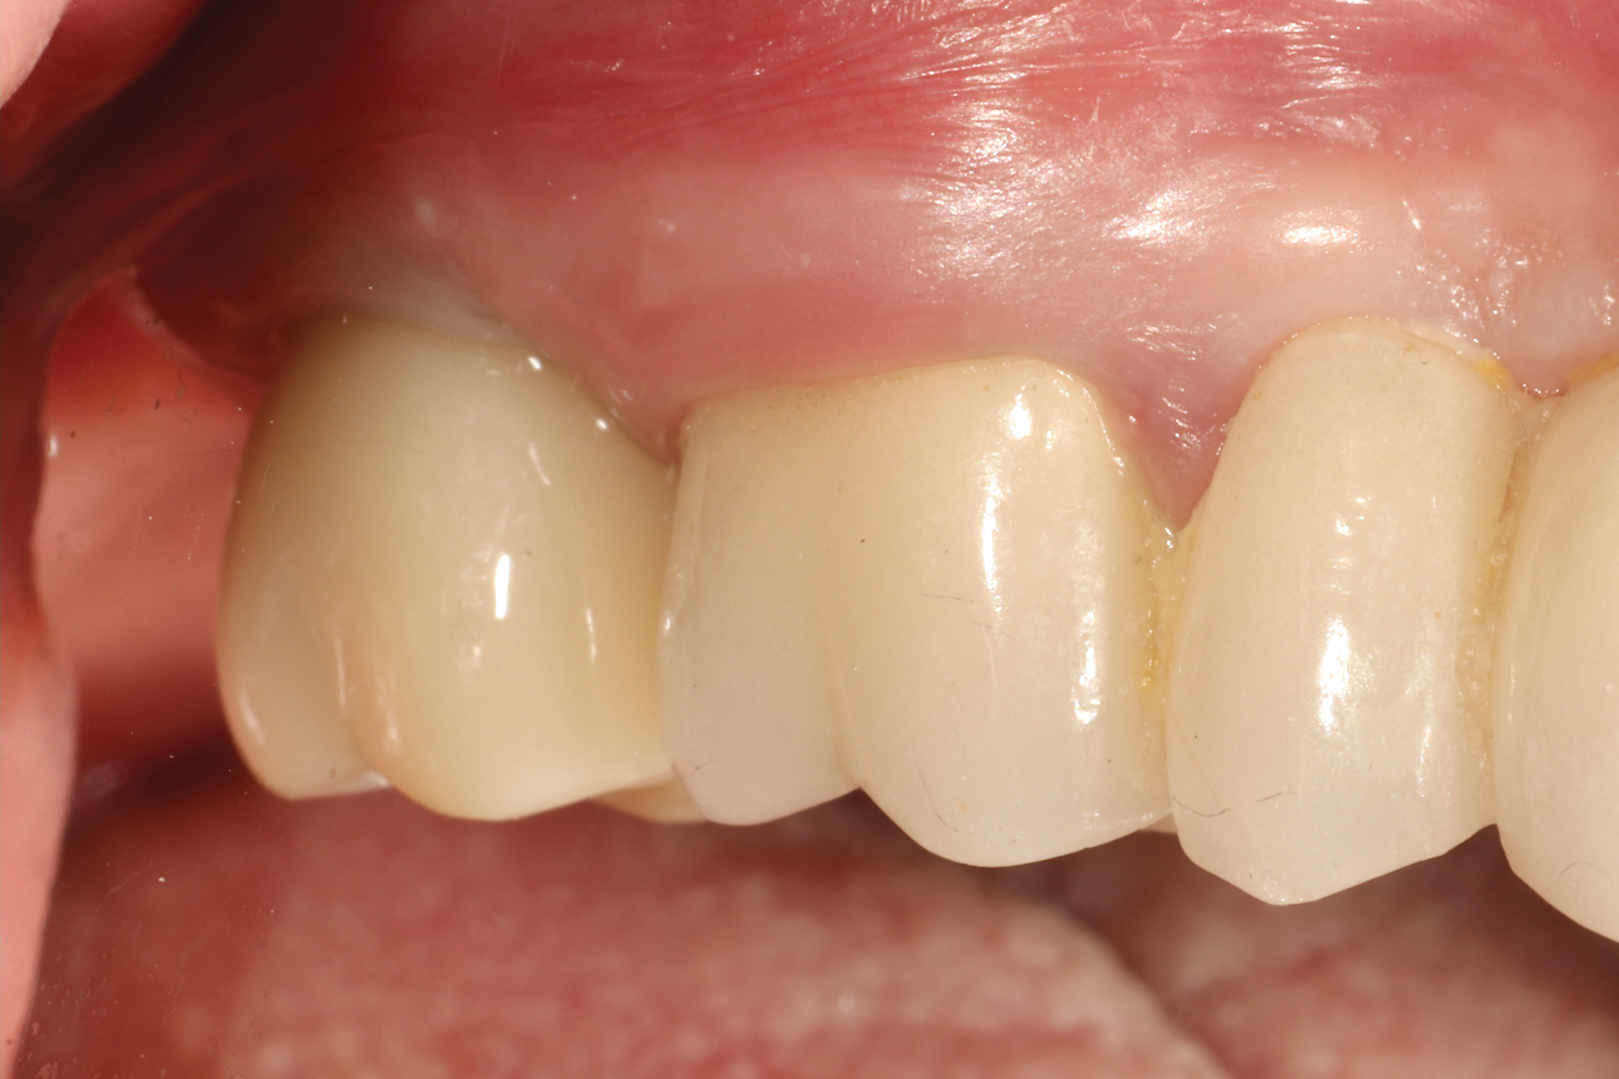

Fig 15. Final zirconia restoration.

Figure 15